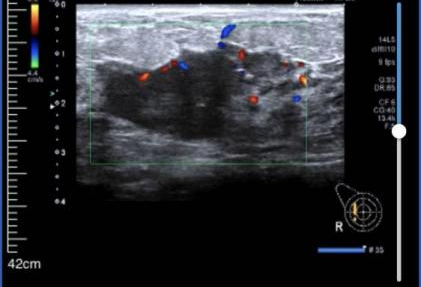

• 乳腺彩超:

1、右侧乳腺相当于9点钟方向距乳头约39.0mm腺体层内见范围约42.5*47.3*21.8mm不均质回声区,形态不规则,边界不清晰,内见丰富血流信号。其旁见大小约7.3*5.5mm低回声区,形态欠规则,边界欠清晰,内见强光点,内见少许血流信号。

2、右侧腋下见大小约31.0*15.8mm淋巴结影像,无正常淋巴门结构,形态尚规则,边界尚清晰,内见丰富血流信号。

超声提示:右侧乳腺实性肿块:BI-RADS 4C类;右侧腋下淋巴结肿大。

图1 乳腺彩超结果(2024-03-01)